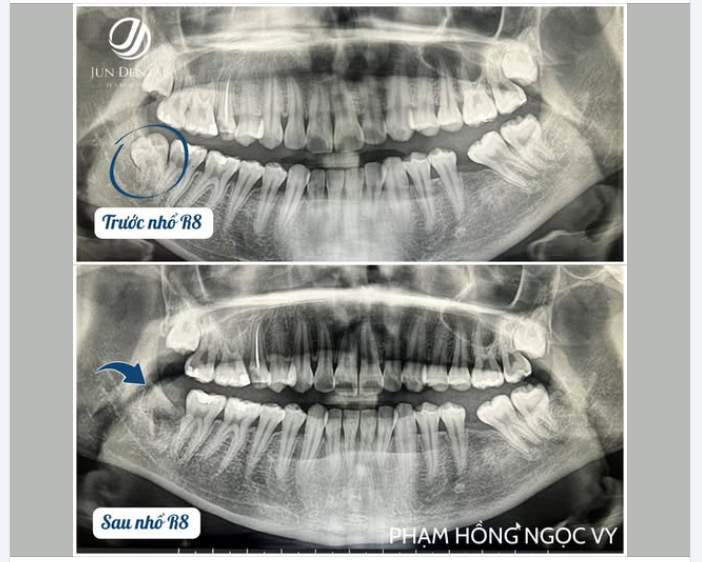

CA LÂM SÀNG: NHỔ RĂNG KHÔN R48 LẬP KẾ HOẠCH CẤY IMPLANT R36 KHÁCH HÀNG PHẠM NGỌC HỒNG VY – JUNDENTAL